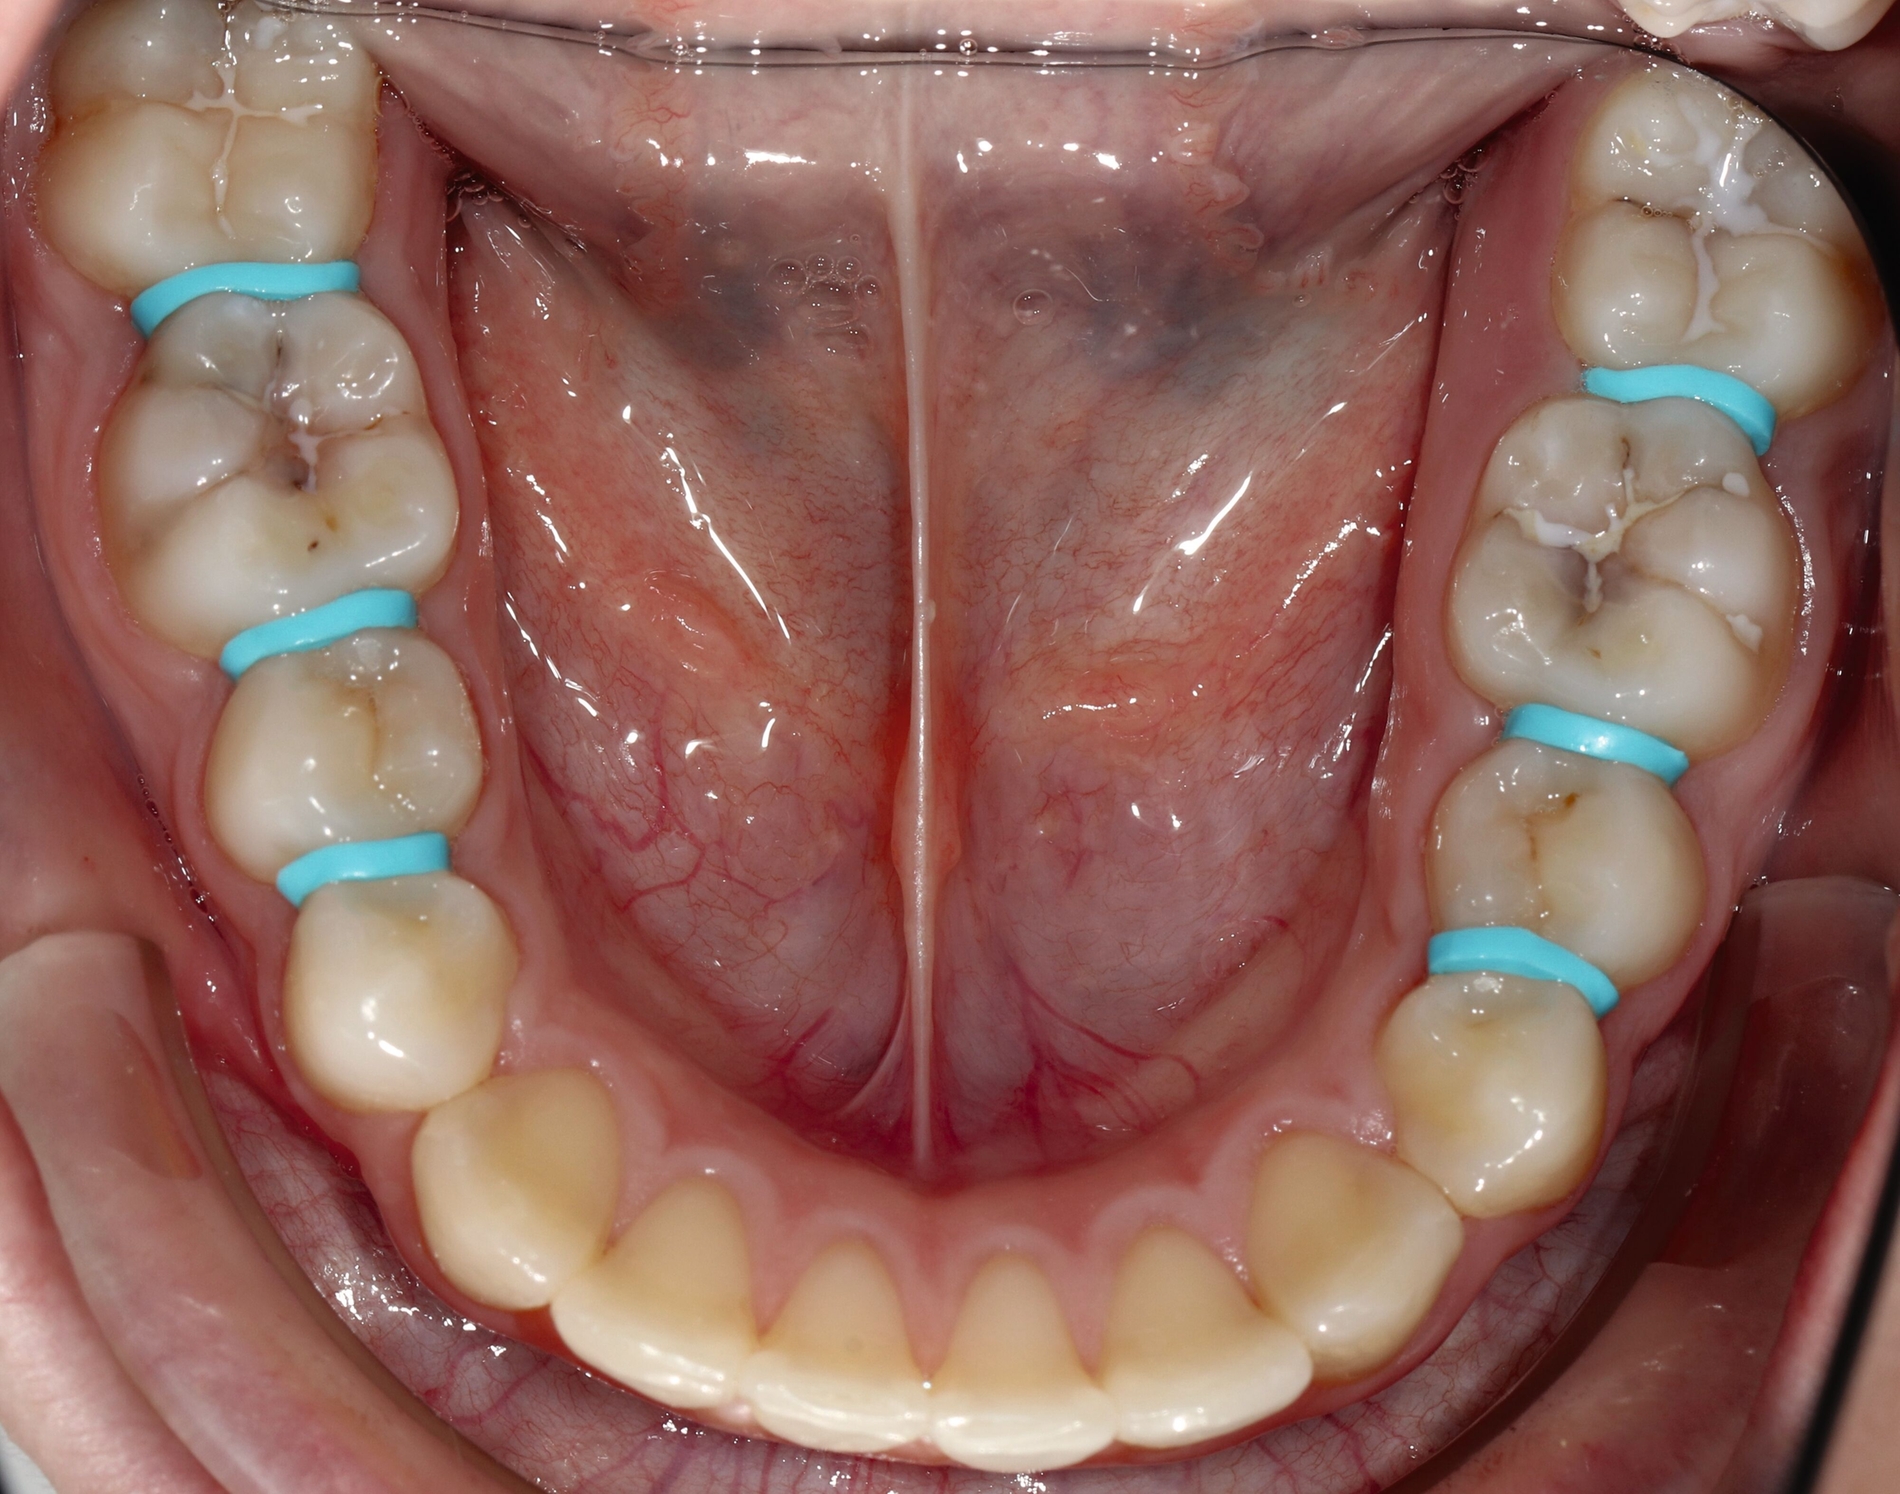

SDF eignet sich auch für die Behandlung von approximalen Läsionen. Besonders interessant wird die Anwendung von Silberfluoriden zur Behandlung von Initialkaries beziehungsweise nicht-kavitierter Karies im kariesaktiven permanenten Gebiss Jugendlicher (Abbildung 8).

Der verkürzt dargestellte Patientenfall zeigt dieses minimalinvasive, innovative und kostengünstige Behandlungskonzept [Ahmed et al., 2023]. Im Kern werden dazu nach vorheriger Diagnostik orthodontische Separiergummis in die Zahnzwischenräume eingesetzt und für circa ein bis zwei Stunden in situ belassen. Direkt nach der Entfernung der Gummis erfolgt eine zügige, direkte klinische Untersuchung der Approximalkaries und eine Applikation von SDF zur Kariesinaktivierung mittels Microbrush.